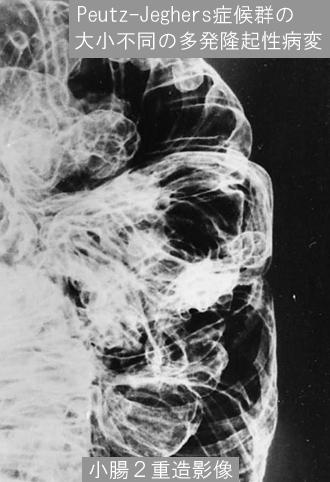

Posted by: Tokyo Pref., 国立癌中心中央病院和九州癌中心共同完成